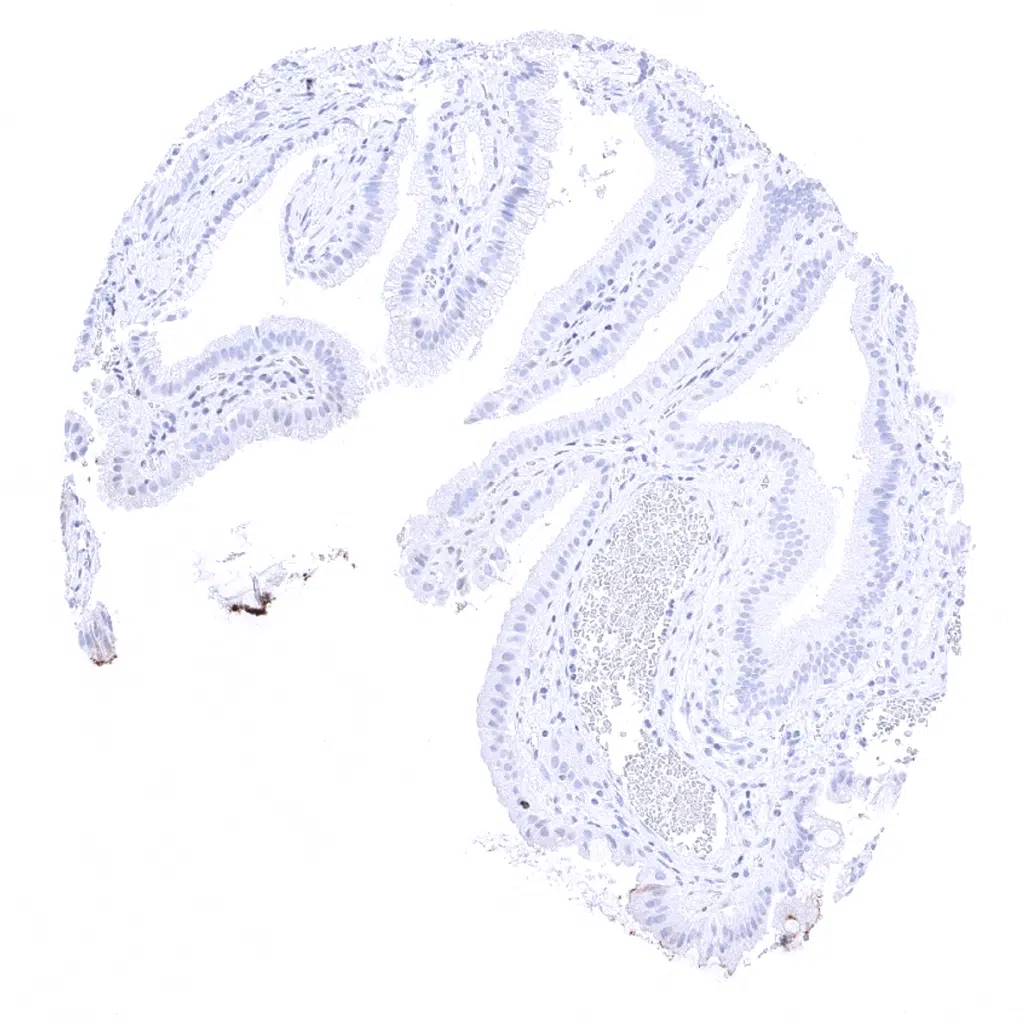

Appendix, mucosa - A strong CD66e staining is seen in epithelial cells of the colon mucosa. The intensity is highest in the surface epithelium.